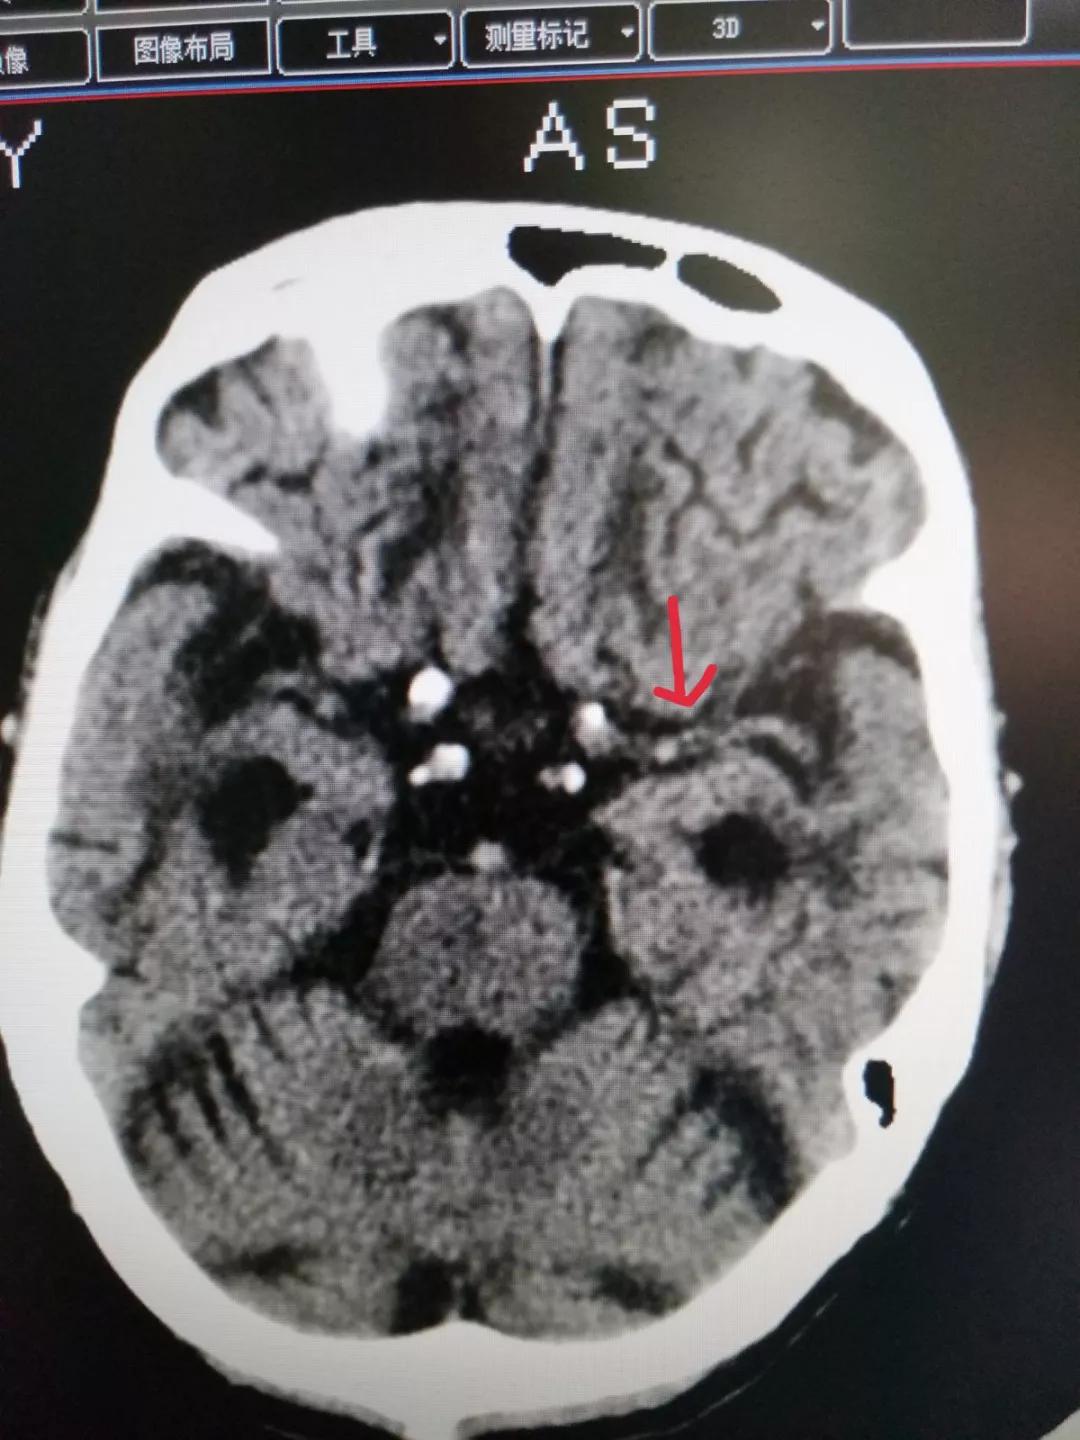

就在开通绿色通道当天,我院就遇到一个急性脑卒中患者。6月4日中午,一名68岁老年男性患者在家站立后突然摔倒,以脑外伤送我院急诊救治。经过检查得知,患者意识模糊,右下肢偏瘫,我院急诊科医师高度怀疑患者系先卒中后摔伤可能。急性脑梗塞每分钟脑细胞死亡190万个,时间就是大脑,病情就是军情;在急诊绿色通道发出紧急通知后,院长陈永雄立刻发出指示:全力启动脑卒中应急绿色通道。业务副院长朱家志、黄志强,医务部主任谢文强协调指挥,脑病中心主任孔凡成和颅脑外科主任任志刚第一时间到现场抢救,放射科、检验科、麻醉科、重症医学科。。。等科室接到命令,全院紧急备战,开辟出阳春市中医院第一条绿色检查通道。迅速完成CT检查后,排除患者脑出血,看到MCA有疑似血栓,迅速完成CTA,见左侧MCA分支少。

颅脑外科主任任志刚看完检查报告后,得出患者要做溶栓治疗的判断,迅速与患者家属进行沟通。急性脑梗塞溶栓的黄金时间是3~4.5小时内,其次不能超过6小时。在任主任反复耐心的解释下,家属终于同意治疗,赶上了治疗最后的末班车。得到患者家属同意后,我院颅脑外科医护团队立刻开始进行溶栓治疗,快速配药,床头执行,娴熟地进行溶栓操作,控制血压,水化治疗……一切有条不紊。术后,患者较前神情语利,右下肢刺痛后能回缩,肢体明显好转。溶栓治疗4天后,患者身体状况良好,饮食语言正常,瘫痪肢体好转,证明了急性脑梗塞急性溶栓治疗的效果。